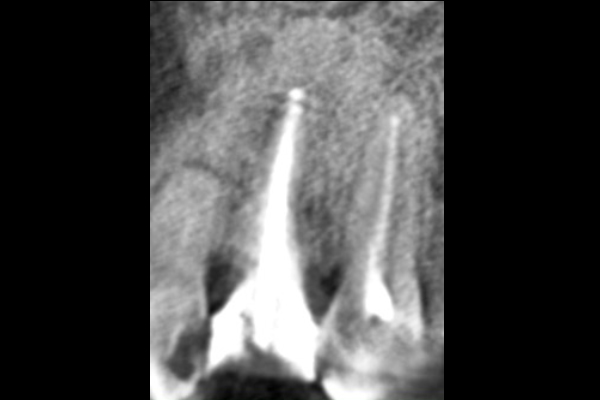

30代男性の小臼歯(奥歯)の症例

- 主訴

- 「奥歯で咬むと違和感がある」「時々歯茎が腫れる」とのことでご来院されました。数週間前から症状があり、他の医院では「抜歯の可能性がある」と言われ、不安に感じていらっしゃいました。

- 期間

- 治療期間2ヶ月、治療回数3回、レントゲン写真で治癒を確認できるまでの期間6ヶ月

- 治療内容

- 1.古い被せ物の除去と虫歯の徹底除去

まず、古い銀歯を外し、内部に広がっていた虫歯を丁寧に取り除きました。

2.マイクロスコープ下での根管治療

唾液などによる細菌の侵入を防ぐ「ラバーダム」を装着し、マイクロスコープ(歯科用顕微鏡)で根管内を数十倍に拡大しながら治療を進めました。複雑な形状の根管の内部まで、汚染された組織を徹底的に洗浄・消毒します。

3.根管充填(こんかんじゅうてん)

根管内が完全にクリーンになったことを確認し、再感染を防ぐために専用の薬剤で隙間なく密閉しました。

4.土台と被せ物の作製

歯の強度を補うための土台を立て、最終的なセラミックの被せ物を作製し、装着しました。

- 治療に伴うリスク

- 少しでも汚染物質が残ると再発のリスクが高まります。